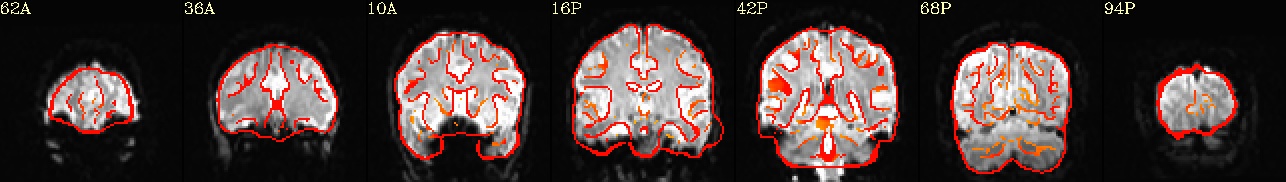

Running Preprocessing and First Level Analysis for sub-08#

All of the preprocessing steps (from setup through scaling) for subject sub-08 were introduced and explained in the example notebook about Preprocessing with AFNI- which is highly inspired by Andy’s Brain Book’s excellent AFNI tutorial. There, it is covered how to use afni_proc.py to generate an automated pipeline, and how to interpret each preprocessing block. In this section, we extend that workflow by adding a regress block to model task-related brain activity using a general linear model (GLM):

Preprocessing and GLM Workflow:

➡️ setup ➡️ tcat ➡️ align ➡️ tlrc ➡️ volreg ➡️ blur ➡️ mask ➡️ scale ➡️ regress 🧠

outputs: includes fitted time series, beta weights, and statistical maps from the GLM.

🧾 regress step: Incorporates timing files, HRF modeling (GAM), symbolic GLTs, and executes 3dREMLfit for improved autocorrelation modeling.